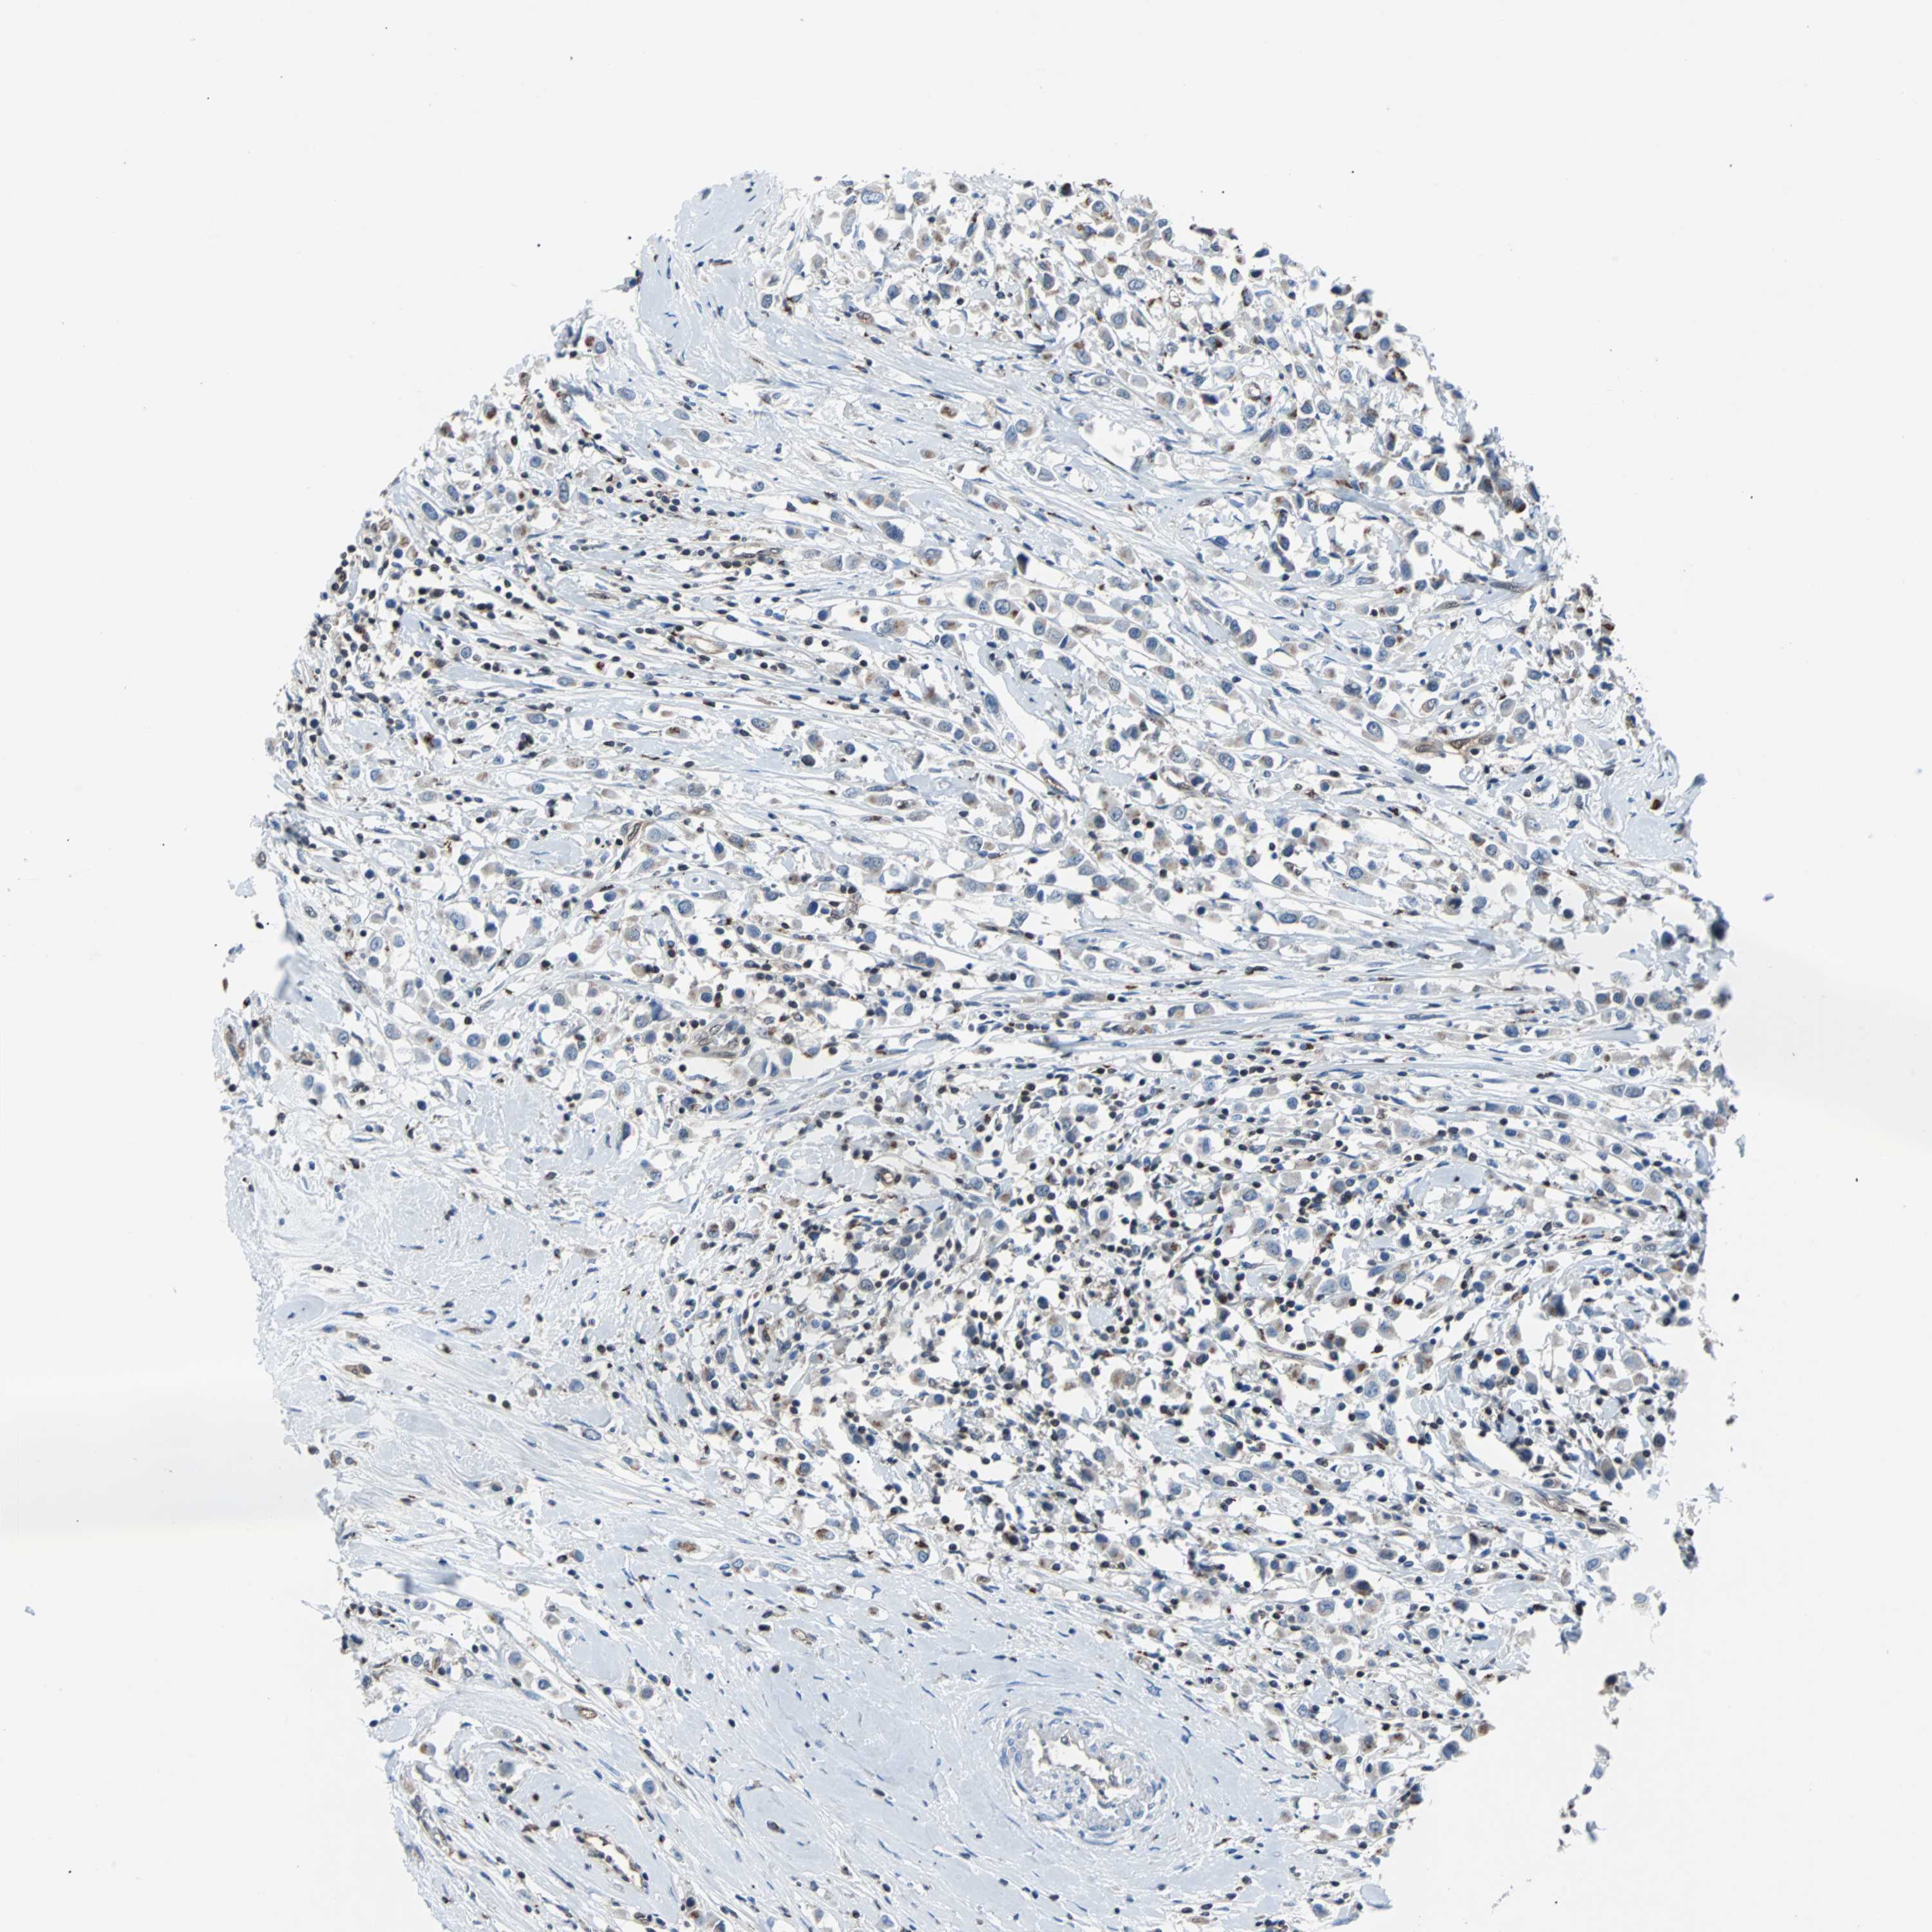

CANCER BREAST CANCER Show tissue menu

BRCA TCGA BRCA VALIDATION PROTEIN EXPRESSION